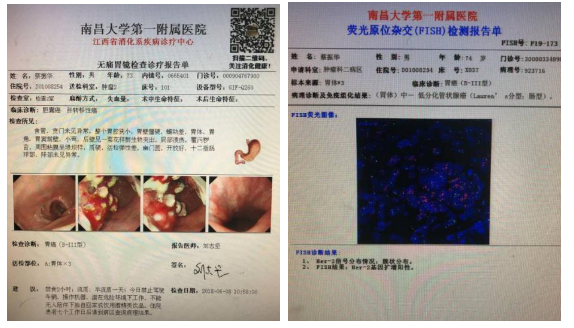

2018.06.08我院胃镜示:胃癌(B-III型)。病理示:中-低分化管状腺癌。

胃镜病理:中-低分化管状腺癌

完善HER2检测

2019-06-05免疫组化CerbB-2(2+),FISH阳性

HER2阳性胃癌患者是一类特殊人群,其是胃癌患者预后不良的孤立预后因素,但其应用抗HER2靶向治疗后OS明显延长。ToGA研究显示HER2阳性晚期胃癌患者,曲妥珠单抗联合化疗组的OS明显高于单纯化疗组。各大指南对于HER2阳性的晚期胃癌患者一线治疗推荐曲妥珠单抗联合化疗。因此,对于每例晚期胃癌,均应强调进行HER2状态规范化检测,尽可能筛选出过表达患者,并在其治疗过程中尽可能应用抗HER2单克隆抗体曲妥珠单抗以延长生存。本病例不足之处在于,HER2状态未在第一时间进行检测,虽患者后续治疗依旧获得不错疗效,但是如果一线就能加上赫赛汀治疗,患者可能获得更大临床获益。